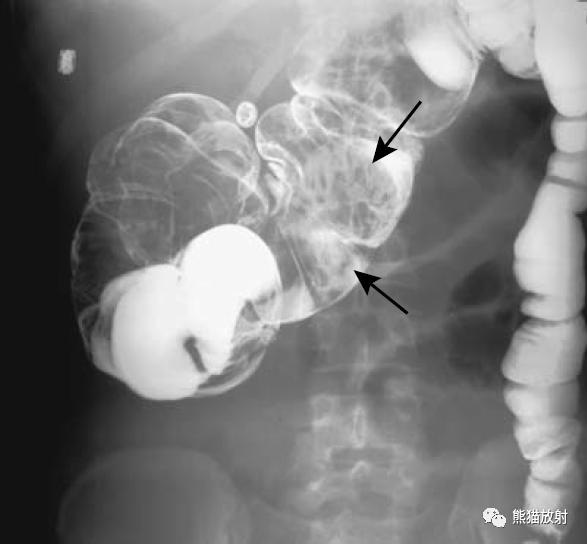

结-结肠肠套叠(箭头)。此例病因很罕见,为结肠子宫内膜异位。

结-结肠肠套叠,由盲肠癌所致。钡灌肠显示横结肠中的肠套叠(箭头),在进一步的压力下,肠套叠移位至升结肠。